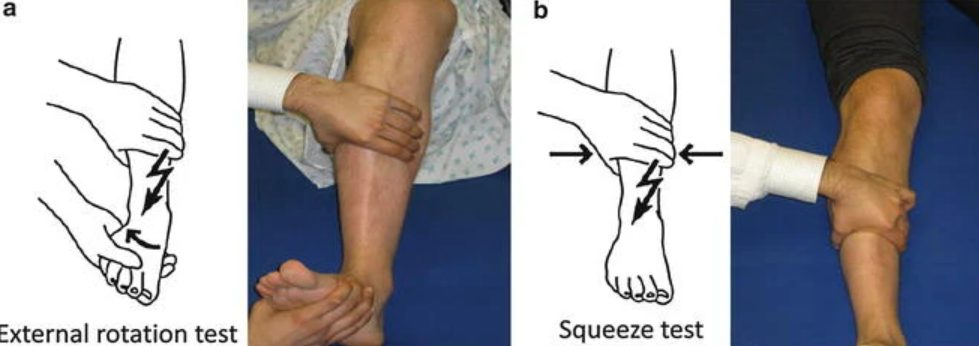

Рис. 12. Стресс-тесты оценки стабильности межберцового синдесмоза

Для диагностики повреждений синдесмоза используют шесть основных клинических тестов, каждый из которых направлен на провокацию боли в области межберцового синдесмоза:

Тест сжатия (squeeze test) — исследующий обхватывает дистальные отделы большеберцовой и малоберцовой костей обеими руками и выполняет компрессию. Боль в области синдесмоза указывает на его повреждение.

Тест наружной ротации (external rotation stress test) — исследующий фиксирует голень одной рукой, а другой выполняет наружную ротацию стопы при нейтральном положении голеностопного сустава. Боль в области синдесмоза свидетельствует о повреждении.